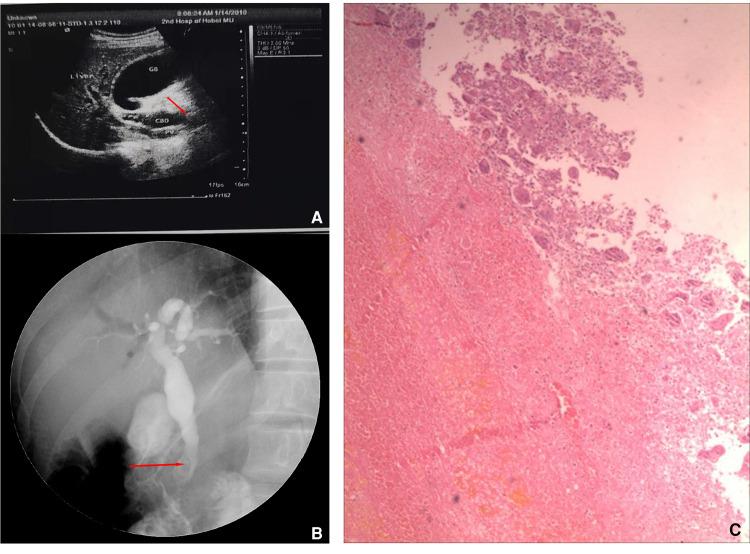

CASE PRESENTATION

In this report, a 48-year-old Chinese man was admitted to our hospital with symptoms of melena. The patient underwent choledochectomy and choledochaljejunostomy for obstructive jaundice 8 years before admission. Endoscopic examination after admission confirmed a mass located at the duodenal papilla. Then, the duodenal papilla and tumor resection were performed, and the histopathology report confirmed the diagnosis of UPS. The patient refused further treatment and died 2 months later due to local recurrence and intrahepatic metastasis.

病例报告

在本报告中,一名48岁的中国男性因黑便症状入院。该患者在入院前8年因梗阻性黄疸接受了胆总管切除术和胆总管空肠吻合术。入院后内镜检查证实十二指肠乳头处有一肿块。随后,进行了十二指肠乳头和肿瘤切除术,组织病理学报告确诊为UPS。患者拒绝进一步治疗,2个月后因局部复发和肝内转移死亡。